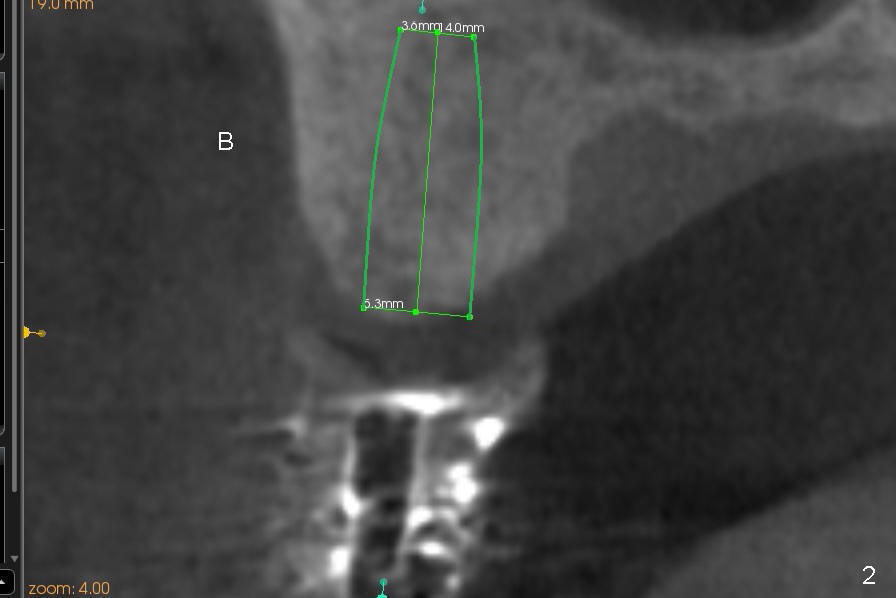

First molar occlusion is planned (1,2). The tooth #3 was extracted a year ago (Fig.1 (CT sagittal section). There is more bone loss distally so that bone graft (red circles) is required post implantation (5.3x14 mm). Buccolingual width is not severely compromised (Fig.2 (coronal section), 3).